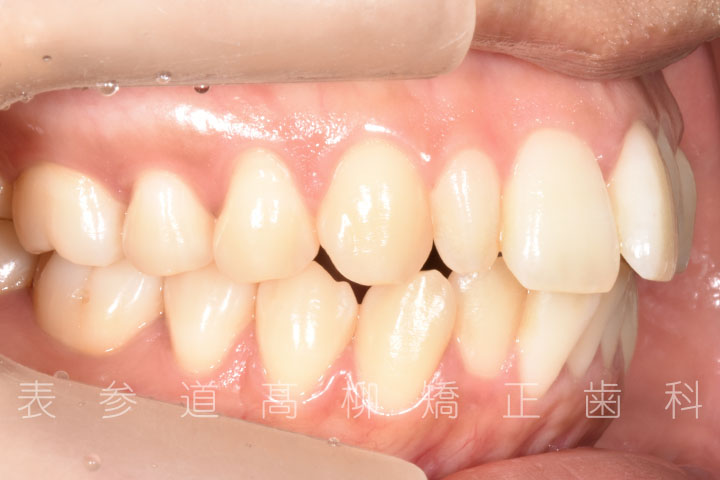

・上顎前突(前歯の前方傾斜)

・上下前歯部叢生(凸凹歯並び)

・前歯部の叢生(ガタガタ感)を改善

・アライナーによる嚙み合わせの微調整

術前術後の比較